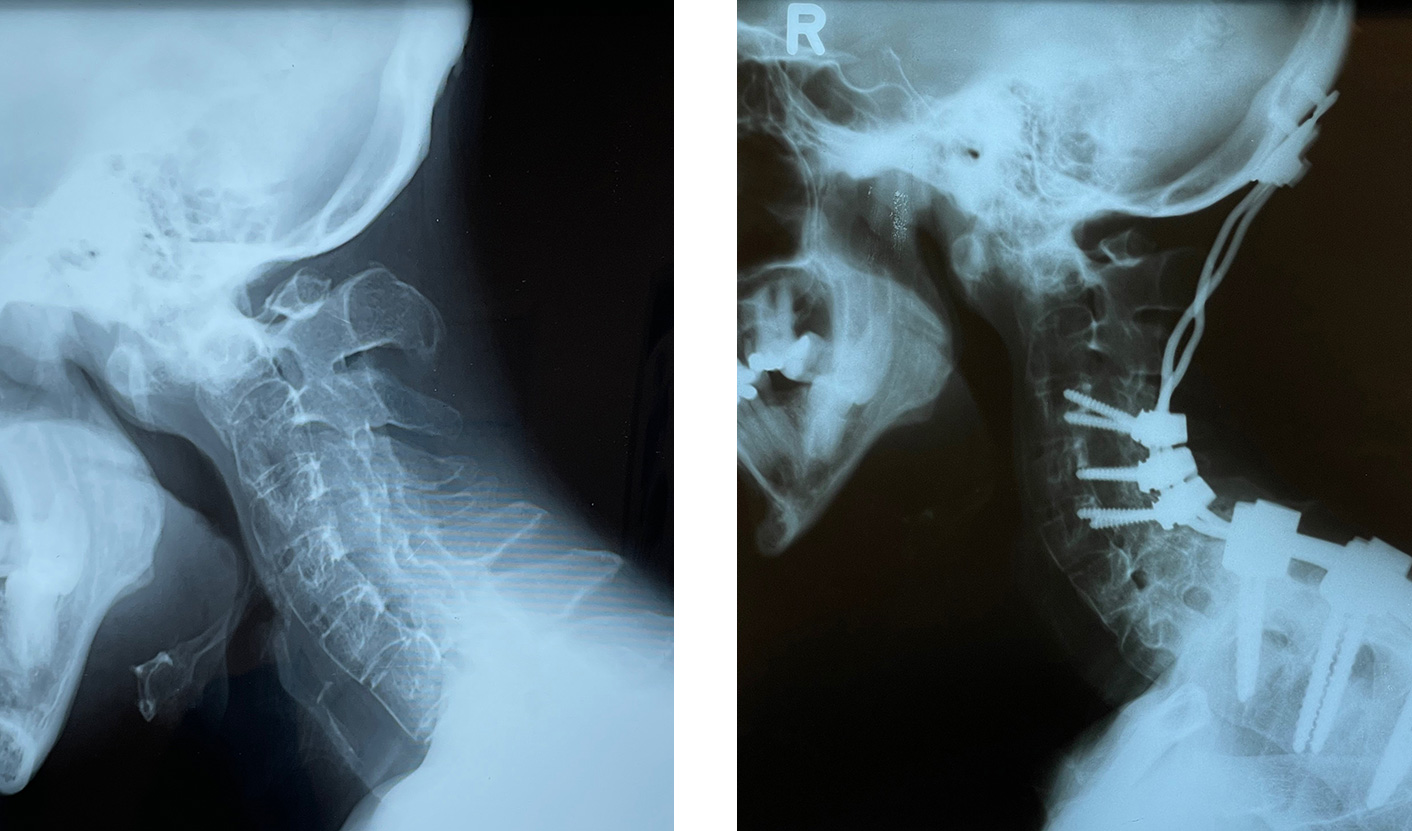

صورة لنفس المريض قبل العملية وبعدها مباشرة ، حيث يمكن ملاحظة أنه بعد العملية يمكنه النظر إلى الأمام مباشرة ، وهو ما كان مستحيلاً قبل العملية

يعيش المريض بشكل طبيعي تمامًا حتى بعد 13 عامًا. تُظهر الصورة أثناء العملية البراغي والقضبان والمكان الذي يتم فيه التحكم في العمود الفقري ، “ينحني” ويعيده ، ثم يتم تثبيته في هذا الوضع. تُظهر الأشعة السينية انحناء العمود الفقري والرأس قبل العملية وموضعًا أنيقًا للبراغي والألواح والقضبان مع وضع تصحيح للرأس والرقبة بعد العملية.